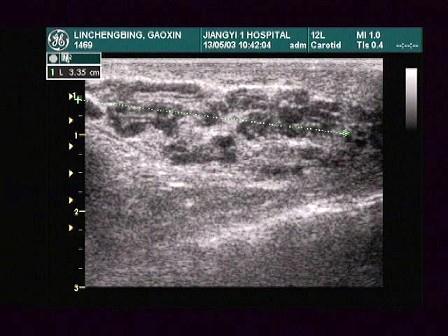

某患者阴囊根部增大,超声声像图如下,最可能的诊断为?(?)A.附睾炎B.斜疝C.精索静脉曲张D.隐睾E.精索鞘膜积液

问题 某患者阴囊根部增大,超声声像图如下,最可能的诊断为?(?)

选项 A.附睾炎 B.斜疝 C.精索静脉曲张 D.隐睾 E.精索鞘膜积液

答案 C